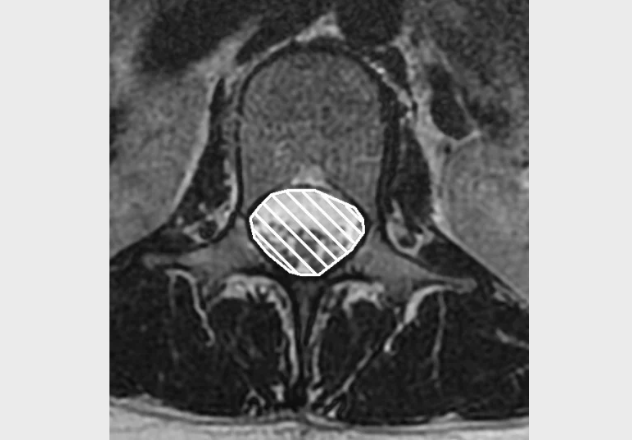

MRI Scan- can be used to view the nerve as it leaves the foramen, and assess any compromise or compression on the nerve. This can be organised BANS.

Image from OpenI – Licensed by CC